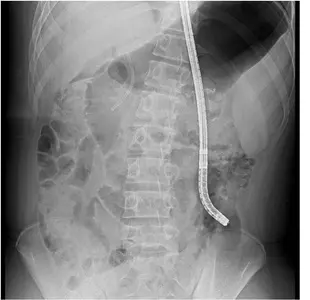

박 교수는 먼저 초음파내시경으로 위와 괴사주머니를 연결하는 통로를 만드는 내강밀착형 스텐트(lumen apposing metal stent)를 삽입했다. 이후 스텐트 내부를 통해 위내시경을 삽입해 췌장의 괴사조직을 직접 제거했다. 내시경적 괴사제거술은 평균 5회가량 시행되지만, 괴사 부위가 워낙 커서 17회의 괴사제거술 끝에 괴사조직을 완전히 제거할 수 있었다.

박 교수는 “경피적 배액술 및 최소침습수술의 도움 없이 총 17회의 내시경적 괴사제거술만으로 골반강까지 확장된 괴사조직을 치료한 국내 첫 사례”라며 “또한 골반강까지 길고 좁게 형성된 괴사주머니 내부를 풍선으로 확장하면서 괴사제거술을 진행한 경우는 전세계적으로도 드물게 보고되고 있으며 천공의 위험성도 매우 높은 고난도 시술에 속한다”고 설명했다.

이 중 내시경적 괴사제거술은 초음파내시경으로 위와 괴사주머니를 연결하는 스텐트를 삽입해 통로를 만든 뒤 위내시경 또는 대장내시경 등으로 괴사조직을 직접 제거하는 방법이다.